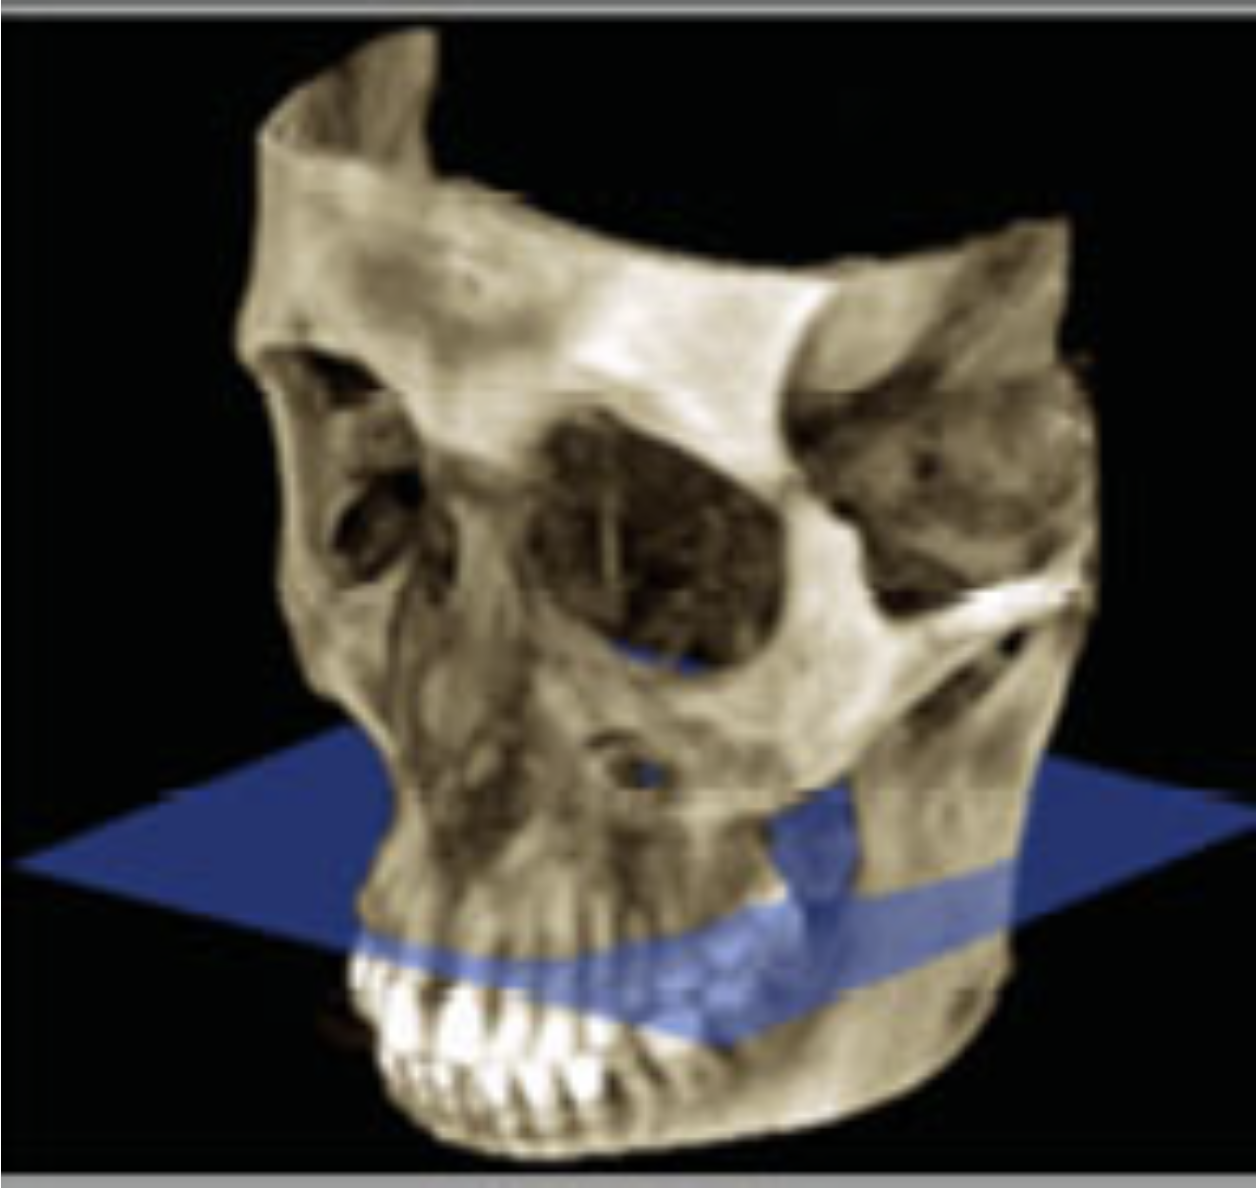

6

Q

What view?

A

3D